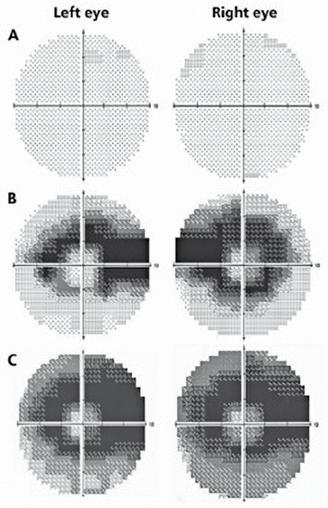

Se recomandă efectuarea unui examen oftalmologic complet înainte de începerea sau în primul an de tratament cu hidroxiclorochină. În cadrul acestui examen, pacienții ar trebui să facă o examinare a fundului de ochi; câmpurile vizuale (fig. 1) și tomografia de coerență optică (fig. 2) ar trebui să fie adăugate în cazul în care există maculopatie. Screeningul anual ar trebui să înceapă după 5 ani de utilizare a medicamentului pentru cei mai mulți pacienți, dar ar trebui să înceapă mai devreme la cei la care există factori de risc majori. Screeningul anual ar

Fig. 1: Modificare progresivă a perimetriei computerizate